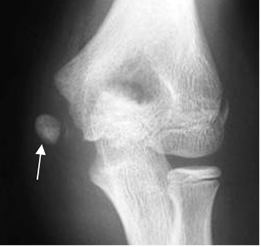

Fig 37 C. Avulsión.

A: Rx AP, B: RM coronal en STIR y C: RM axial en STIR. Avulsión del epicóndilo medial, con cambios inflamatorios en los tejidos blandos.